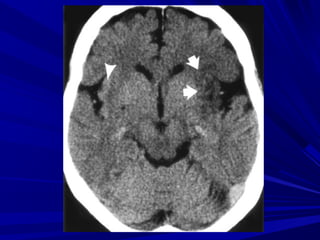

Phân biệt xuất huyết và vôi hóaPhân biệt xuất huyết và vôi hóa

Vôi hóa đối xứng, không có hiện tượng phùVôi hóa đối xứng, không có hiện tượng phù

não và không có hiệu ứng choán chnão và không có hiệu ứng choán chỗỗ

Xuất huyết không đối xứng, có phù não chungXuất huyết không đối xứng, có phù não chung

quanh và có hiệu ứng choán chổquanh và có hiệu ứng choán chổ

Ðo mức độ cản quangÐo mức độ cản quang

Vôi hóa > 120 HuVôi hóa > 120 Hu

Xuất huyết = 40-90 HuXuất huyết = 40-90 Hu

Xuất huyết hay vôi hóa ?

Xuất huyết hay artefact ?